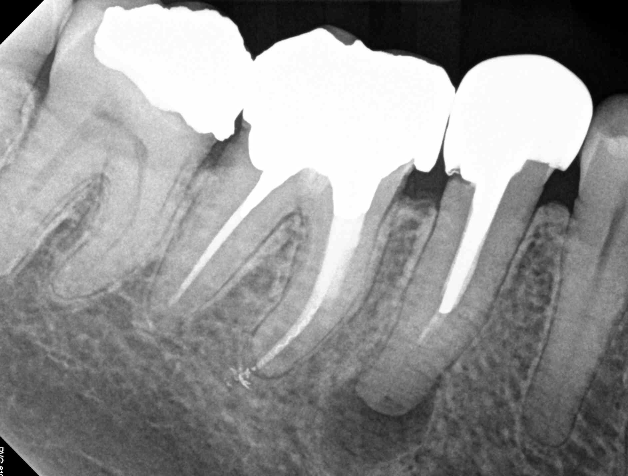

<p>what stands out about this bitewing</p>

what stands out about this bitewing

• there should be a root fill between the end of the post-crown on the LR5 but it is missing